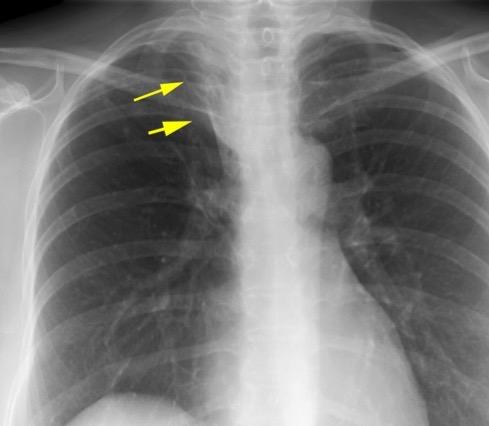

PANCOAST. SÍNDROME

DE

Masa apical acompañada de dolor del hombro, síndrome de Horner y atrofiade los músculos de la mano. 5% de los Ca. de pulmón. 95% de los casos debido a a Ca. de pulmón no microcítico.

Adenocarcinoma con destrucción de 1ª costilla y linfangitis peritumoral.

Puede deberse también a linfoma, neoplasias pleurales, ca de tiroides, infecciones, hongos, etc.

Hutchings HE et al. Treatment patterns and outcomes in patients with Pancoast tumors: a national cancer database analysis . J Thorac Dis . 2023 / Bruzzi JF, et al.. Imaging of non–small cell lung cancer of the superior sulcus. Radiographics 2008.